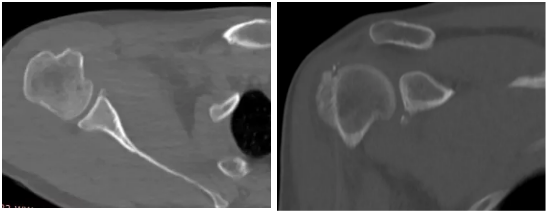

病例1

病史摘要:男性,44歲,跌傷致右肩關(guān)節(jié)疼痛數(shù)天,活動(dòng)不利。

CT圖示:右側(cè)肱骨后外上方局部骨皮質(zhì)塌陷,連續(xù)性中斷(箭頭);肩胛盂前下份邊緣變鈍,見(jiàn)高密度分離小骨片影(三角形)。